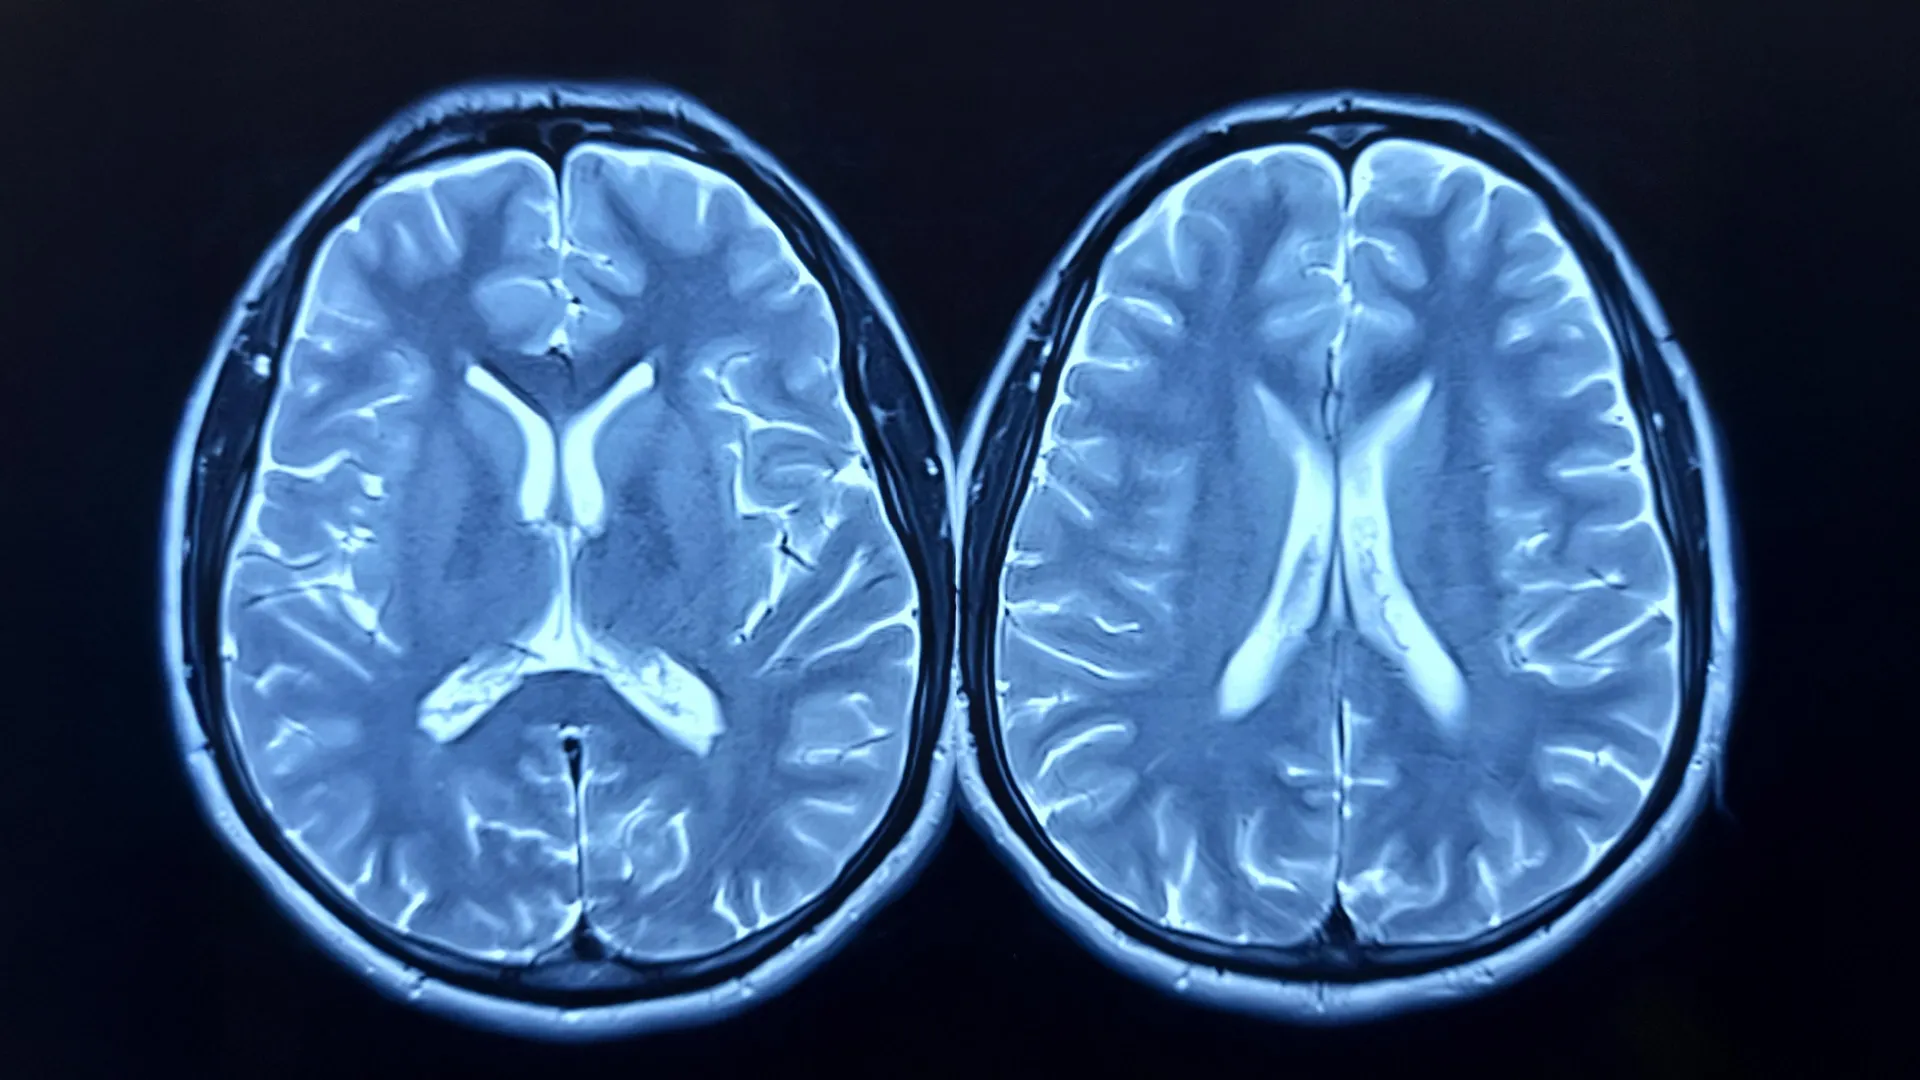

Scientists examined MRI scans of nearly 15,000 adult Britons, taken both before and after the COVID-19 pandemic. Utilizing advanced AI methods, they determined that during the pandemic, the human brain aged, on average, 5.5 months faster than before 2020. This phenomenon was labeled an unexpected consequence of the pandemic.